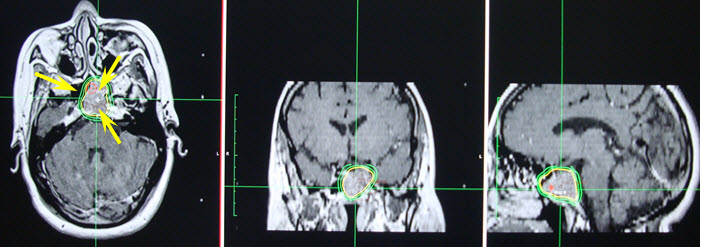

Hình 1. Hình ảnh khối u tuyến yên xâm lấn xoang hang

Hình 3. Hình ảnh đường đồng liều trên 3 mặt phẳng.